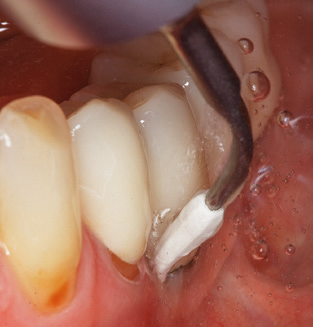

Una buona illuminazione del campo di lavoro facilita notevolmente il processo. Il sistema utilizzato dagli autori ottiene questo risultato grazie a un anello LED 5x integrato nel manipolo. Naturalmente, viene offerta anche una serie di consigli di lavoro per diverse indicazioni. Un inserto diritto, utilizzabile universalmente, è lo strumento di base necessario per la pulizia meccanica dei denti naturali (Fig. 5a e b). Sono disponibili anche inserti curvi, che consentono l'accesso alle forcazioni esposte, per le aree difficili da raggiungere nella regione posteriore (Fig. 6).

Naturalmente, anche i consigli di lavoro per la pulizia delle superfici degli impianti sono indispensabili per SPT nei pazienti dotati di impianti. L'inserto per la pulizia dell'impianto in questo casoi è caratterizzato dal suo design affusolato ed esagonale. Questo design consente una penetrazione leggera e atraumatica nella tasca perimplantare e mostra buone prestazioni di pulizia (Fig. 7).